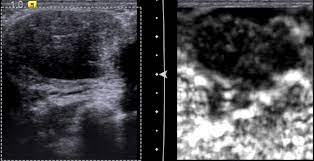

Cysts, tumors, and growths will appear as dark areas on the scan. Breast ultrasound uses sound waves to make a computer picture of the inside of the breast. What does a solid mass look like in an ultrasound breast image? Ultrasound of triple negative breast cancer. This is a network of thin tubes (vessels) and nodes that carry a clear fluid called lymph around the body. A breast ultrasound is most often done to find out if a problem found by a mammogram or physical exam of the breast may be a cyst filled with fluid or a solid tumor. Solid lesions can be a little brighter or darker than the surrounding tissue, and the way to evaluate these on ultrasound is to look closely at the margins or the outer edges of the nodule. In the table the differences in ultrasound appearances are listed. Ibc is a rapidly progressive, aggressive form of breast cancer associated with a low overall survival rate. On the flip side, there are benign (not cancerous) breast changes which can mimic breast cancer as well. What does breast cancer look like on a mammogram? American cancer society, 9 oct 2017. Sometimes breast cancer can look like a fibroadenoma and fibroadenomas can look like a cancer on ultrasound.

Breast Biopsy Ultrasound Guided from www.radiologyinfo.org However, a dark spot on your ultrasound doesn't mean that you. It is the most common cause of cancer death in women. in 2005 alone, 519 000 deaths were recorded due to breast cancer. this means that one in every 100 deaths worldwide and almost one in every 15 cancer deaths were due to breast cancer. Other ultrasound findings that suggest breast cancer include: A breast ultrasound is most often done to find out if a problem found by a mammogram or physical exam of the breast may be a cyst filled with fluid or a solid tumor. If a solid lump shows on the scan you might need to have. You might not need any further tests if everything looks normal. Tumor size is an important factor in breast cancer staging, and it can affect a person's treatment options and outlook. This high amount of echo results in a bright white spot appearing on the ultrasound image.

This breast cancer ultrasound image shows changes related to breast cancer that are not seen as microcalcifications or a mass or lump. Any area that does not look like normal tissue is a possible cause for concern. If your breast tissue is too dense for a mammogram. Ultrasound imaging allows better evaluation of the status of the axillary lymph nodes in patients with ibc, an important step in determining extent of disease prior to initiation of chemotherapy. If a solid lump shows on the scan you might need to have. It is the most common cause of cancer death in women. in 2005 alone, 519 000 deaths were recorded due to breast cancer. this means that one in every 100 deaths worldwide and almost one in every 15 cancer deaths were due to breast cancer. With ultrasound, the radiologist will probably be trying to get a sense of the internal texture of the breast lesion and surrounding area. Physical examination and mammogram can be more accurate in some settings. If there are calcifications within the nodular dcis, one may be able to see these on ultrasound as white flecks. The images that a breast ultrasound produces are in black and white. A diagnostic mammogram is used to check for breast cancer when there is a sign or symptom of disease. A breast ultrasound is most often done to find out if a problem found by a mammogram or physical exam of the breast may be a cyst filled with fluid or a solid tumor. To look more closely at a.

Any area that does not look like normal tissue is a possible cause for concern. Below are images of dcis on breast ultrasound. Ultrasound is not used on its own as a screening test for breast cancer. Ultrasound (us) shows an irregular, hypoechoic (dark gray) spiculated mass (arrow), highly suspicious for cancer. This is because it may miss some early signs of cancer.